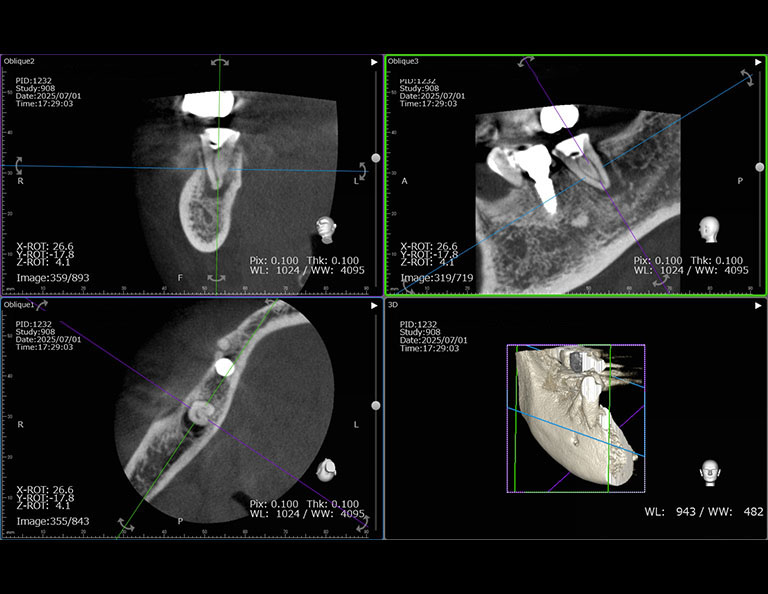

術前のCTです。

歯根の周囲の骨吸収が認められます。

根管治療後のCTです。

歯根の周囲の骨吸収もだいぶ改善されました。